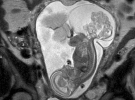

Мшканка Техасу Маргарет Бомер на 16-му тижні вагітності зробила чергове УЗД. Лікарі сказали, що у дитини є пухлина в зоні куприка. Єдиною надією на порятунок була операція. Лікарі мали розкрити живіт і дістати плід вагою 538 г на 20 хв.,а потім повернути назад. Шанси вижити у дівчинки були 50/50.

Після операції Маргарет поклали в лікарню на збереження. Дитина розвивавалася всередині матері ще 12 тижнів - до повних 36 тижнів вагітності.

Лінлі Хоуп Бомер народилася вдруге за допомогою кесаревого розтину. Важила 2400 г.

"На 23-му тижні пухлина блокувала роботу її серця і загрожувала серцевою недостатністю. Вибір був між тим, аби дозволити пухлині заволодіти її організмом, і тим, щоб дати їй шанс вижити. Для нас це було просте рішення: ми хотіли дати їй життя", - каже мати дівчинки.

За словами лікаря Даррелла Каса із Дитячого ембріонального центру Техасу, тератома - найпоширеніша пухлина у новонароджених, з якою вони стикаються.

Причина розвитку пухлини невідома, хоча вона зустрічається у дівчаток в чотири рази частіше, ніж у хлопчиків. Новоутворення трапляється один раз на 30-70 тис дітей.